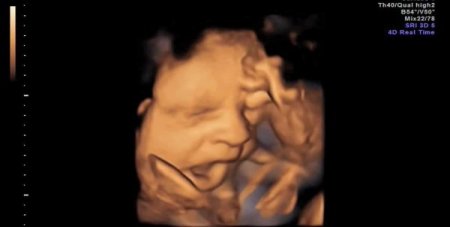

Araştırmayı yürüten ekibin başındaki Nadja Reissland, “Anne karnındaki bebeğin esnemesinin fonksiyonunu ve önemini halen bilmiyoruz. Ancak elde ettiğimiz veriler, esnemenin cenin gelişimi ve bebeğin sağlık belirtileri ile bağlantılı olabileceğini gösteriyor. Rahimdeki bebeğin esneme sıklığı, erken gebelikte beynin olgunlaşması ile ilgili olabilir” açıklamasını yaptı.

Reissland ve ekibinin gözlemi, gebeliğin 24 ve 36. haftaları arasındaki 8 kız ve 7 erkek bebekte yapıldı. Esnemenin 28. haftadan itibaren azaldığı, erkek ve kız bebeklerde önemli bir farklılığın olmadığı ortaya çıktı. CİHAN